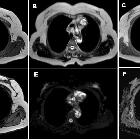

different imaging modalities in the evaluation of normal and diseased thymus. MRI chest in a 45-year-old female patient shows a rather well-defined superior anterior mediastinal lobulated soft tissue lesion eliciting heterogenous low T1 (a) and mixed signal in T2WI signals (b), with areas of restricted diffusion in out-of-phase image (d) compared to in-phase (b, c) image. It elicits diffusion restriction (e, f) with ADC value = 0.8. Histopathological confirmation revealed terato-dermoid tumor